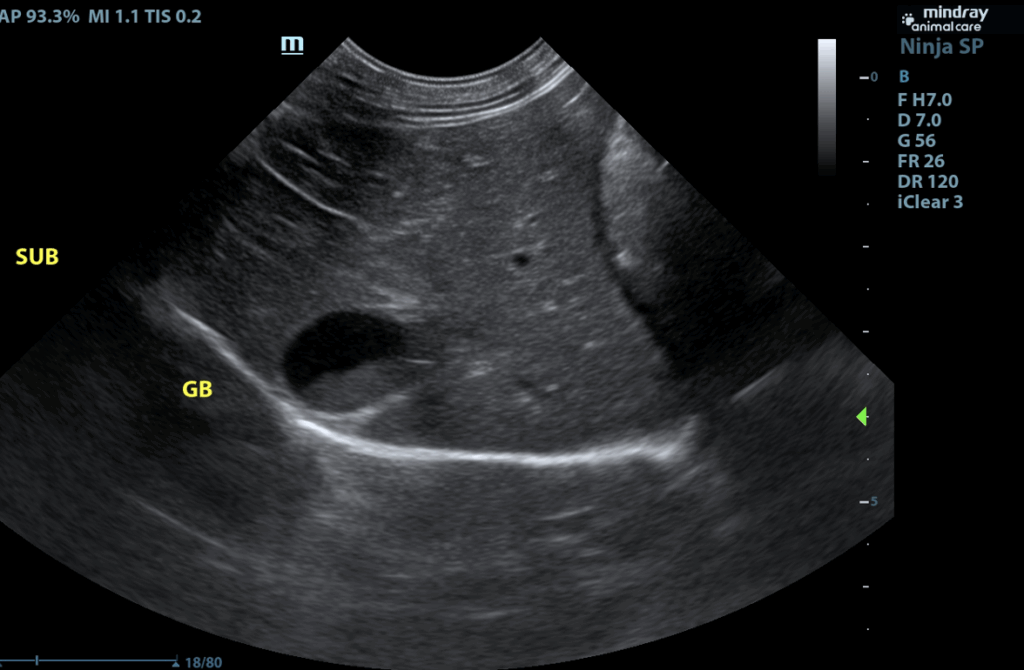

The liver is subjectively normal in size with normal smooth curvilinear peripheral contour. Parenchyma is appropriately hypoechoic to the spleen in echogenicity and appropriately mildly coarse and homogenous in echotexture. No focal lesions are observed. Visible vasculature and biliary tree appear normal without distension or congestion. Gallbladder is moderately distended with anechoic bile as well as suspended and gravity dependent echogenic debris. The wall is smooth without visible thickening. There is no evidence of cystic or CBD dilation. There is no evidence of effusion or inflammation.

- Mild gallbladder debris – Cholecystic debris is of unknown clinical significance. It can be seen with biliary stasis from fasting or illness, however, it can also be associated with hepatobiliary disease in cats and should be interpreted in combination with clinical signs such as nausea, inappetence, cranial abdominal discomfort and/or laboratory changes such as increased ALP and/or increased Tbili.